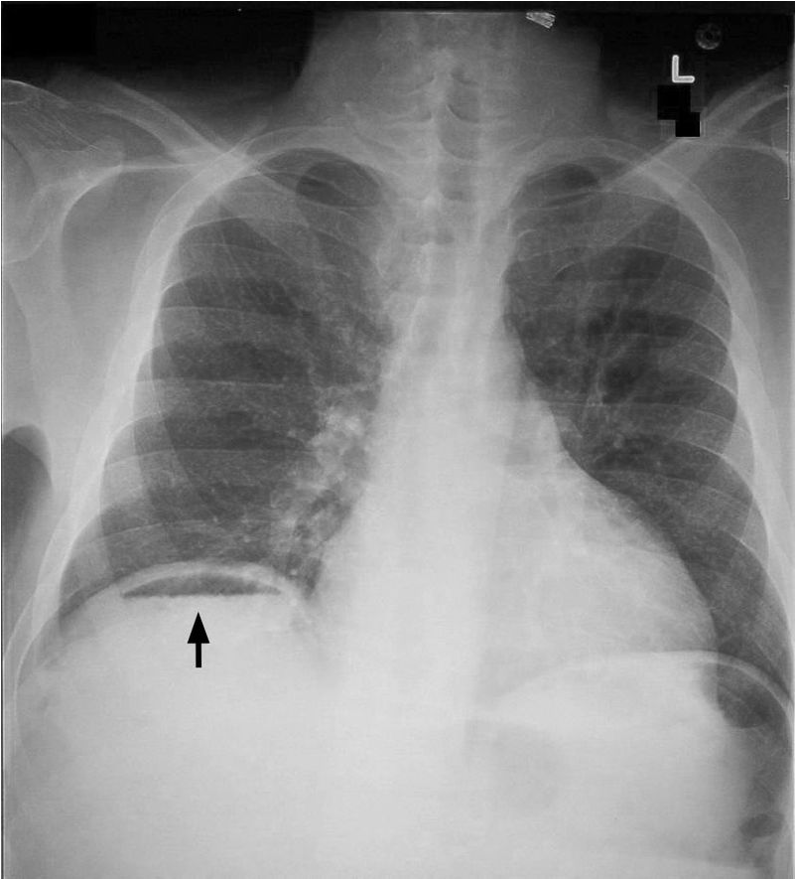

- An erect chest X-ray (eCXR) – for evidence of bowel perforation.

Perforation - air - can be found normally after surgery